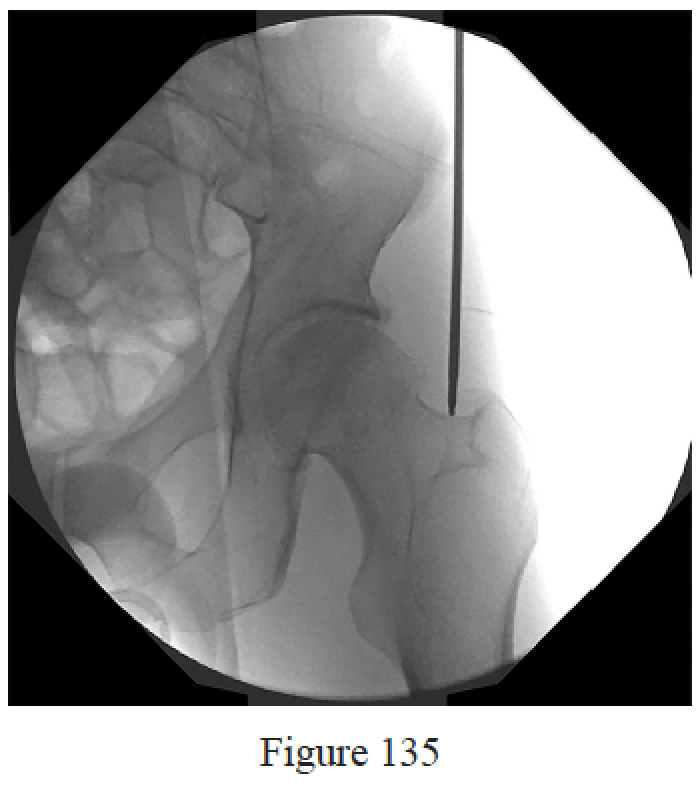

Figures 10a and 10b are the emergency department radiographs of a 32-year-old healthy man who is involved in a motor vehicle collision. He has an isolated injury. What is the best next step?

Callaghan JJ, Liu SS, Haidukewych GJ. Subcapital fractures: a changing paradigm. J Bone Joint Surg Br. 2012 Nov;94(11 Suppl A):19-21. doi: 10.1302/0301-620X.94B11.30617. Review. PubMed PMID: 23118374.

Bhandari M, Devereaux PJ, Swiontkowski MF, Tornetta P 3rd, Obremskey W, Koval KJ, Nork S, Sprague S, Schemitsch EH, Guyatt GH. Internal fixation compared with arthroplasty for displaced fractures of the femoral neck. A meta-analysis. J Bone Joint Surg Am. 2003 Sep;85-A(9):1673-81. PubMed PMID: 12954824.